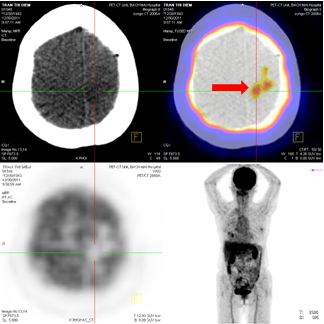

Hình 5: Hình ảnh PET/CT có tổn thương cung sau xương sườn số 5 bên trái, và khối u não vùng đỉnh trái

Chụp MRI sọ não: Sau xạ phẫu 6 tháng bằng dao gamma quay: khối u não tan biến hoàn toàn

Trước điều trị: u não 20×19mm

Sau điều trị 6 tháng: u tan hoàn toàn

Hình 6: Hình ảnh chụp MRI sọ não sau 6 tháng xạ phẫu bằng dao gamma quay: Khối u não di căn vùng đỉnh trái tan hoàn toàn

Trước điều trị: tổn thương thùy đỉnh trái 2 cm

Sau điều trị 6 tháng: tổn thương tan hoàn toàn

Hình 8: Hình ảnh PET/CT toàn thân sau 6 tháng điều trị: Khối u não vùng đỉnh trái tan hoàn toàn.